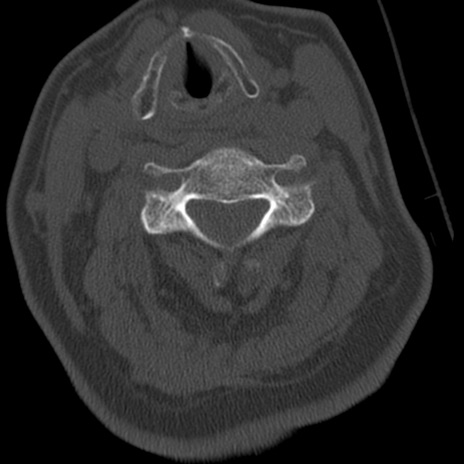

症例50 頚椎CT(横断像)

頚椎CT